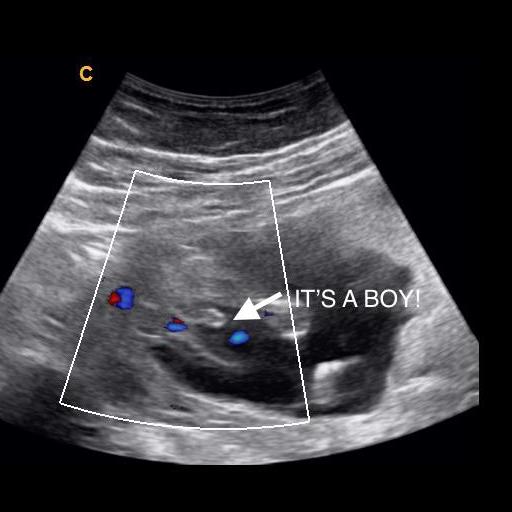

what does a boy look like on ultrasound

A 20 Week Male Gender Guess | Ultrasound Unwrapped

Gender Ultrasound..boy? {picture} | BabyCenter